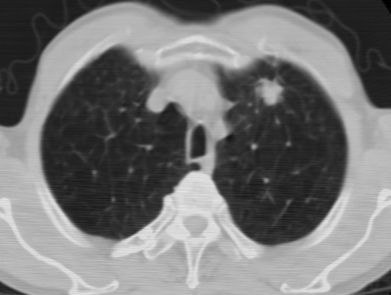

标题: CT24783:m71,既往肺心病史3年,现咳嗽,憋喘。 [打印本页]

标题: CT24783:m71,既往肺心病史3年,现咳嗽,憋喘。

1、左肺上叶spn,毛刺+分叶+血管集束征,考虑周围型肺癌可能性大

2、全小叶性肺气肿。

1)左肺上叶周围型肺癌可能。2)两肺全小叶型肺气肿。

左上周围型肺癌,全小叶型肺气肿。